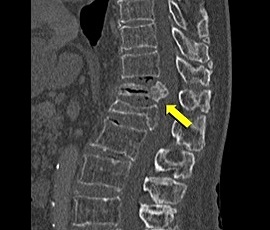

[非血管系IVR] 圧迫骨折(胸椎) 手術:経皮的椎体形成術(PVP)

CT画像

治療後